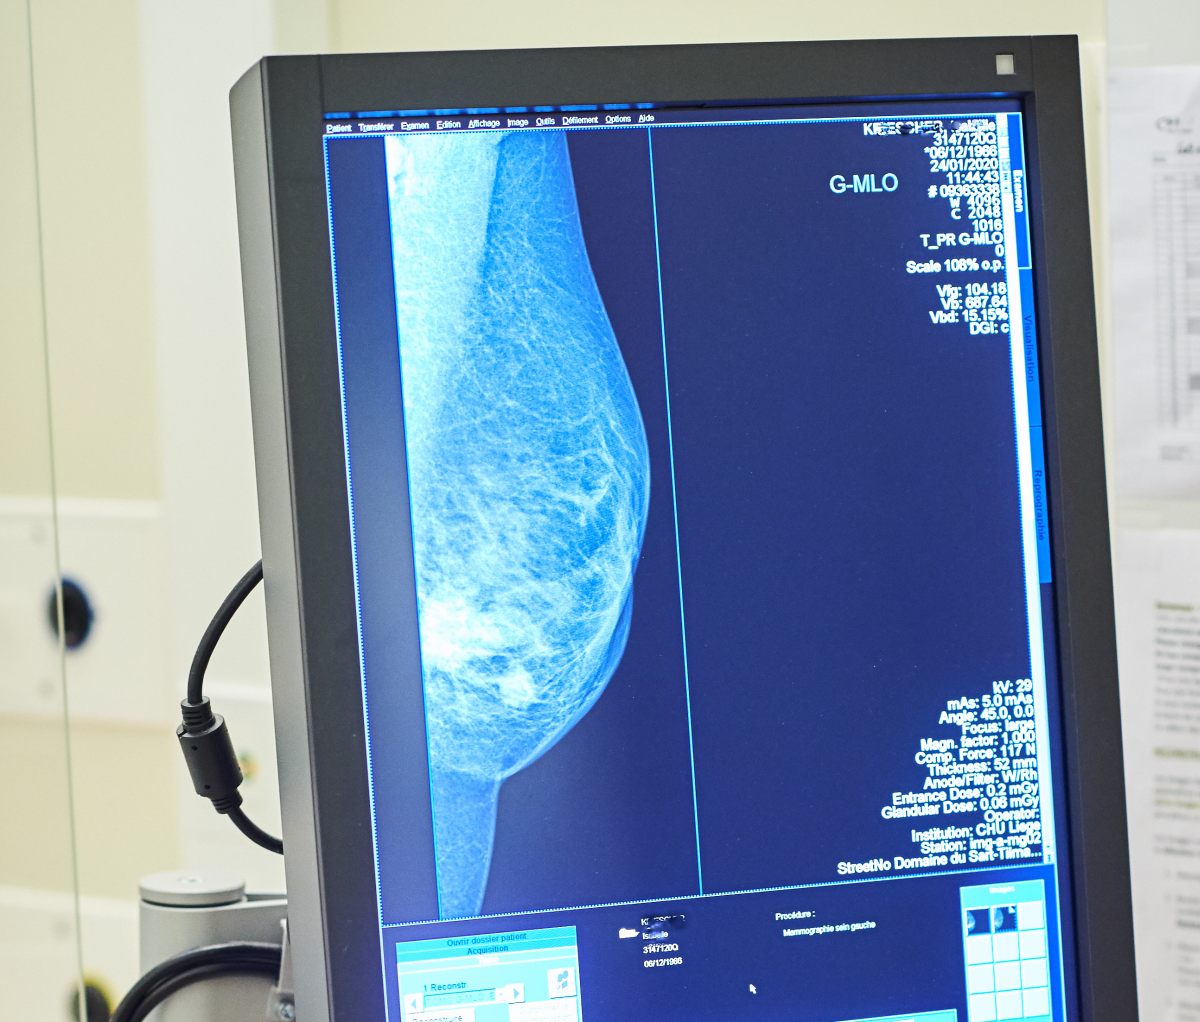

ROMA (ITALPRESS) – A quasi tre mesi dall’istituzione dell’apposito fondo nazionale di 20 milioni di euro, i test genomici per il carcinoma mammario non sono ancora disponibili gratuitamente in tutta Italia. “Per migliorare la qualità di vita delle pazienti e permettere risparmi di preziose risorse pubbliche bisogna accelerare le procedure affinchè questi esami siano disponibili senza alcuna spesa. Per questo chiediamo un intervento diretto e immediato del Ministero della Salute affinchè approvi al più presto il decreto attuativo”. E’ questo l’appello che sostiene Europa Donna Italia, il movimento per la tutela dei diritti delle donne con tumore al seno che a inizio 2021 ha avviato la campagna nazionale “Chemio: Se Posso la Evito”. I principali risultati dell’iniziativa sono stati presentati oggi in una conferenza stampa virtuale. In poco più di due mesi sono state raccolte oltre 15.000 firme ad una petizione on line. Sono poi stati raggiunti oltre 564mila utenti del web attraverso un’intensa attività sui principali social media.

“Abbiamo ottenuto buoni risultati e un ottimo sostegno da parte di pazienti, caregiver, clinici e semplici cittadini – afferma Rosanna D’Antona, presidente di Europa Donna Italia -. Si tratta di una chiara testimonianza che conferma quanto sia sentita la necessità della personalizzazione delle cure, soprattutto in questo momento difficile caratterizzato dal Covid-19. Europa Donna Italia si è battuta perchè non solo in Lombardia, Toscana e Provincia Autonoma di Bolzano – dove i test sono finanziati da fondi regionali – ma in tutta la Penisola si possa evitare la somministrazione di chemioterapie inutili. Sono circa 8.000 le pazienti che, ogni anno, ricevono queste cure anche se non ne hanno necessità. Ringraziamo il Governo e il Parlamento per quanto fatto finora. Bisogna però al più presto emanare il provvedimento che renda effettivamente utilizzabili i test genomici senza costi per le donne”.

“Questi esami rappresentano una fonte di risparmio importante per i conti pubblici – aggiunge il professore Carlo Tondini, direttore Oncologia Medica dell’Ospedale Papa Giovanni XXIII di Bergamo -. Nello studio BONDX, condotto in Regione Lombardia su 400 pazienti, abbiamo provato a quantificare da un punto di vista economico i vantaggi ottenuti. La ricerca ha evidenziato come l’uso di due test, da 2.000 euro ciascuno, abbia evitato una chemioterapia dal costo di 7.000 euro. Il risparmio diretto sulla spesa farmaceutica regionale ammonta a circa 3.000 euro per paziente a cui vanno aggiunti i costi indiretti per malati e caregiver. Abbiamo, inoltre, evitato ad una donna di essere sottoposta ad una chemioterapia, dopo l’intervento chirurgico, e preservato così la sua qualità di vita evitando effetti collaterali”.